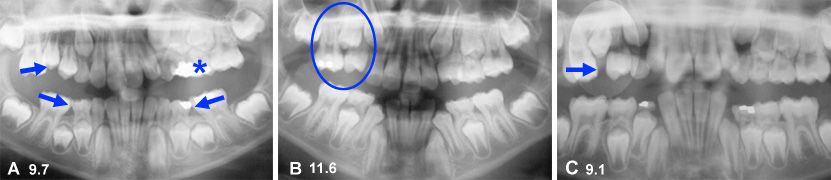

Problèmes d’éruption

La radiographie panoramique de cette fille de 10 ans permet de déceler plusieurs problèmes d’éruption (encerclés) pour lesquels il est indiqué d’intervenir. L’extraction de dents temporaires peut aider à changer la direction d’éruption anormale des dents permanentes.

Éruptions canines

(B) Radiographie montrant un patron d’éruption différent pour les deux canines permanentes supérieures qui sont encore dans la gencive.

(A) Du côté droit, la canine se dirige de façon parallèle à l’incisive latérale et il n’y a pas de déplacement de l’incisive latérale (flèches jaunes).

(C) Du côté opposé, la canine entre en collision avec l’incisive latérale qui s’incline vers l’arrière et bascule vers l’avant (flèches bleues). L’extraction sélective de dents temporaires peut aider à influencer la direction d’éruption et diriger la canine gauche chez ce garçon de 9.9 ans.